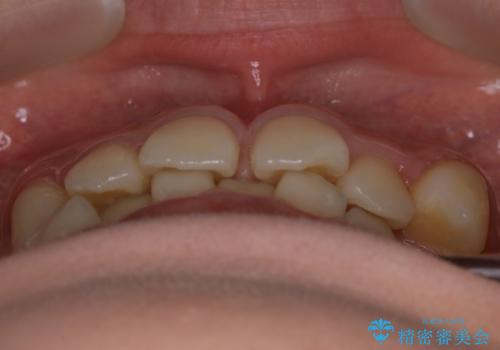

- 上の前歯のすきっ歯と下の前歯のガタつきを主訴にご来院されました。

噛み合わせの改善も同時に進めつつ、主訴の部分も効率的に治していくためマウスピース装置でゴムかけを行いながら治療を進めていきました。

正中離開(すきっ歯)

真ん中の歯が左右に開いてしまい隙間ができてしまう状態を「正中離開」といい、俗にすきっ歯と呼ばれています。

隙間を埋めていく方向に歯を移動させることで改善していくケースが多く、比較的治りやすい不正咬合のひとつとされています。

しかしながら、歯が捻じれていたり、噛み合う歯との位置関係によっては治療が難しくなる場合があります。